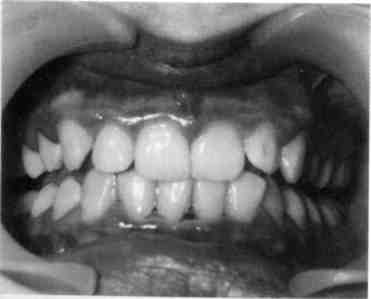

Хронический катаральный гинги­вит может возникнуть не только вследствие микробного налета, но и других местных причин — дефектов пломбирования и ортодонтического лечения, аномалий прикуса, при­крепления уздечек и тяжей слизи­стой оболочки, коротких уздечек губ, мелкого преддверия полости

рта, кариозных полостей придесне-вой локализации, изменения соста­ва и уменьшения количества рото­вой жидкости, а также различных видов травм (рис. 8.1).

Жалобы при хроническом ката­ральном гингивите слабо выраже­ны, основные из них — кровоточи­вость при приеме жесткой пищи и чистке зубов, запах изо рта. Слизи­стая оболочка десны синюшная, слабоотечная, выражен вазопарез (медленно исчезающий след при надавливании пинцетом). Проба Шиллера—Писарева положитель­ная. Степень тяжести гингивита определяется совокупностью об­щих изменений в организме ребен-

Рис. 8.1. Хронический катаральный гингивит.

ка и степенью вовлечения деснево­го края в воспалительный процесс. Гингивит легкой степени тяжести характеризуется вовлечением в па­тологический процесс межзубных сосочков, средней степени — во­влечением в процесс межзубного и маргинального участков десны; тя­желой форме гингивита прису­ще поражение всех отделов дес­ны (межзубных сосочков, марги­нального и альвеолярного участ­ков).